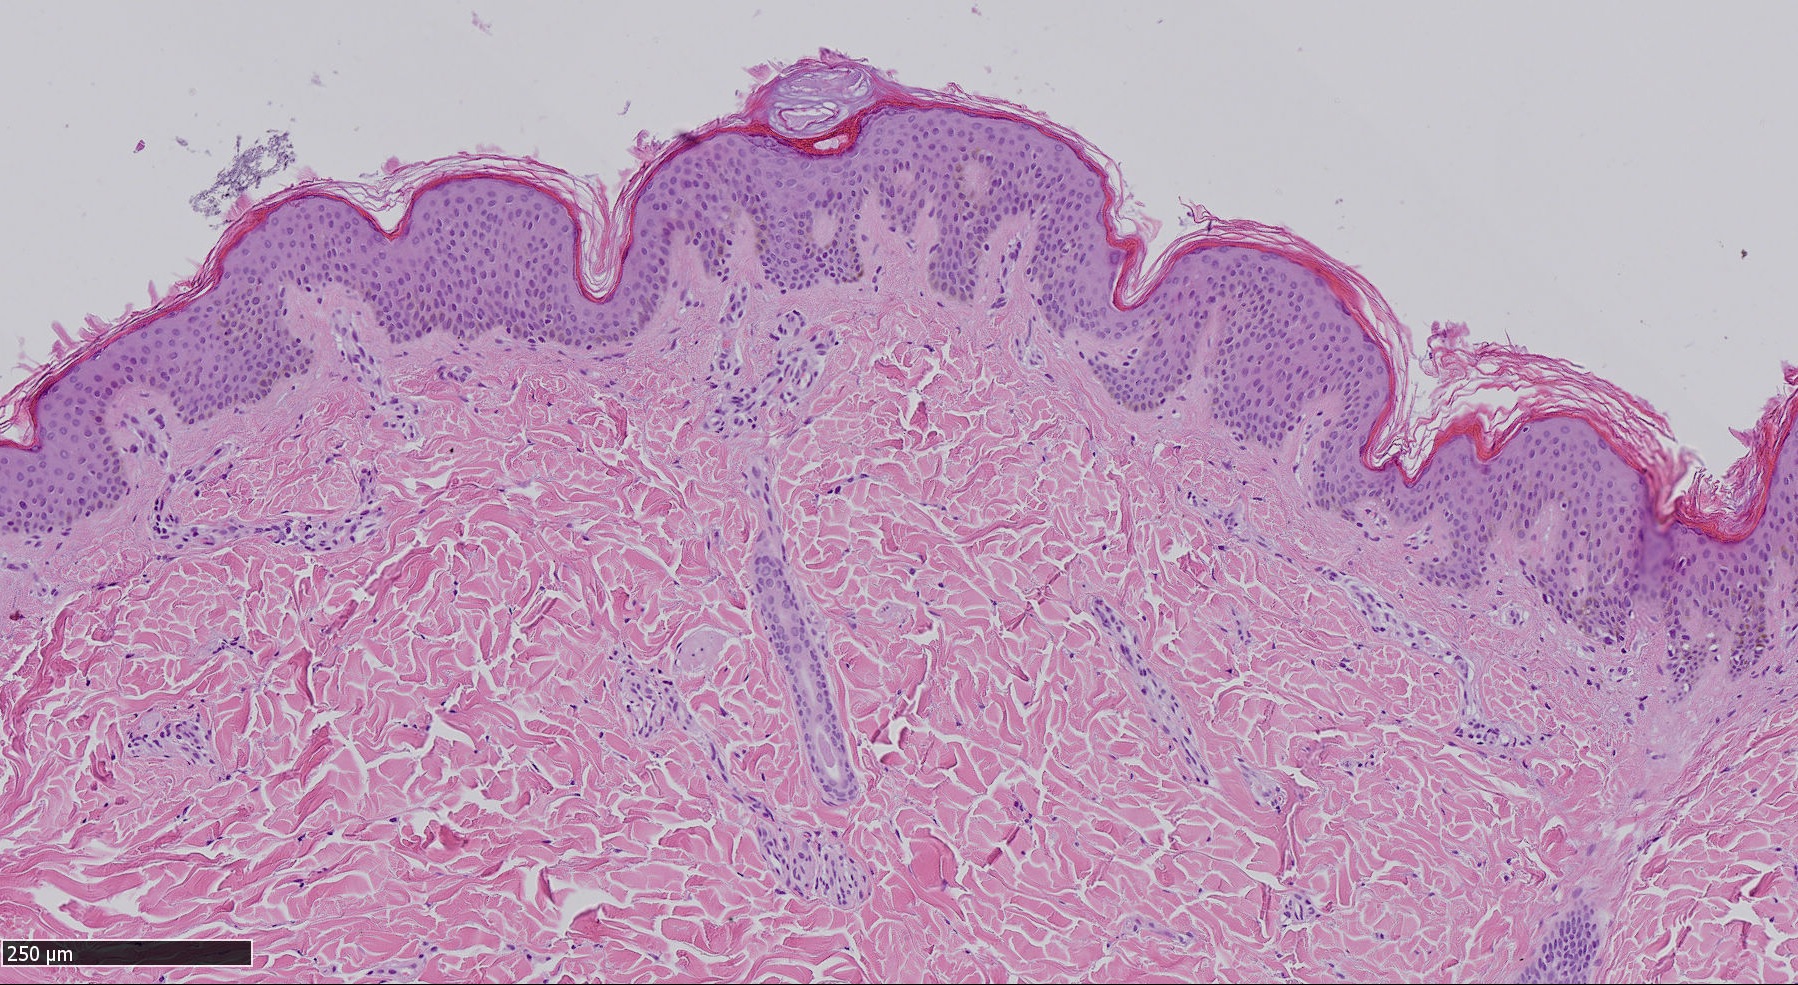

A Sassari, nella struttura di Anatomia Patologica nel 2018 sono stati diagnosticati 67 melanomi infiltranti, quando cioè la membrana basale dell’epidermide è superata ed è infiltrato il derma a vari livelli di profondità, e 30 in situ, cioè melanomi non invasivi contenuti nella membrana basale dell’epidermide. Dai dati a disposizione della struttura sassarese, la sopravvivenza a 5 anni è descritta con un range variabile nelle diverse realtà dal 75 per cento a circa il 90 per cento.